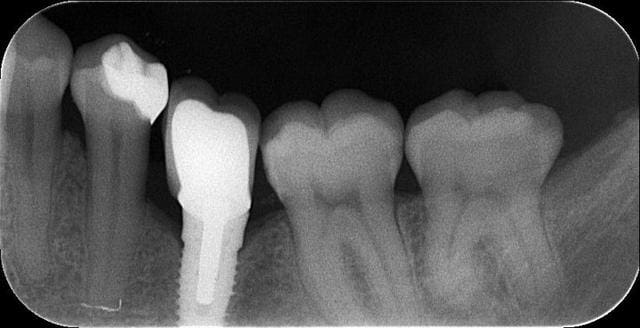

j'ai posé deux easy avec le biseau enfoui dans l'os. A 3 mois, pose des piliers de cicatrisation et un mois plus tard pose de la prothèse.

manifestement l'os ne reste pas en place à ce niveau

je prendrai un cliché dans 3 mois pour évaluer ce qu'il advient de la zone mésiale du col de l'implant distal.

46 47 xvjblf - Eugenol

46 47 pose kiaay7 - Eugenol